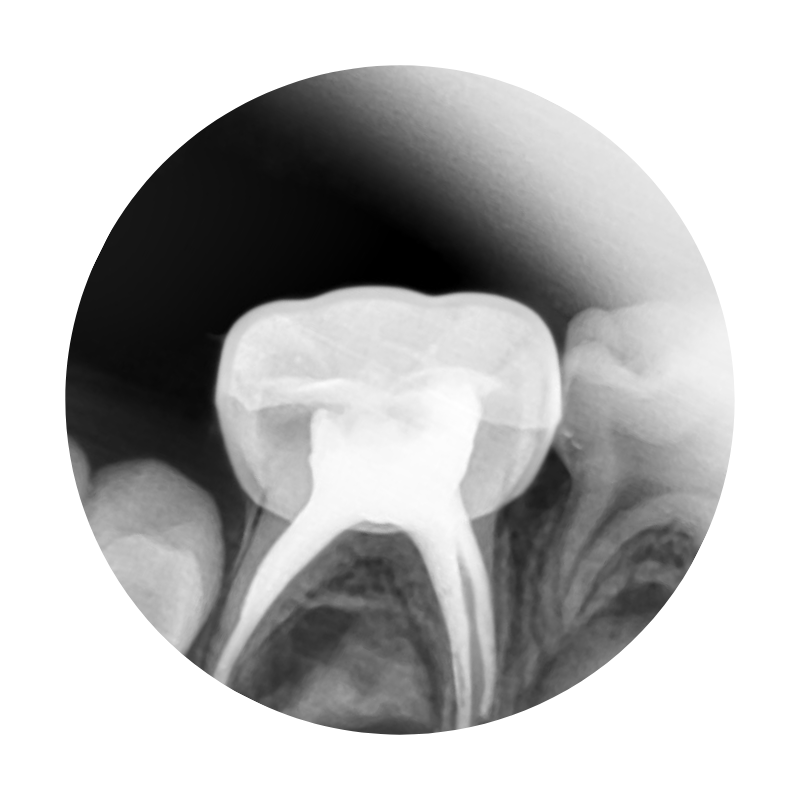

RCT for kids in Nagpur: Painfree and single sitting

RCT and Crowns

When baby teeth are damaged by deep cavities, they may need root canal treatment. Since the tooth nerve or pulp is removed, they often require extra protection. Specially designed dental crowns for kids safeguard the tooth and allow it to function normally.

If a baby tooth is lost early, crowns or space maintainers help preserve the gap. This makes sure permanent teeth erupt in their correct position and lowers the risk of crowding or misalignment later.

Different crowns are available depending on your child’s needs. Tooth-coloured options like zirconia or composite strip crowns blend naturally with the smile, while stainless steel crowns are valued for their durability. Your kid’s dentist can guide you better on the most suitable choice.